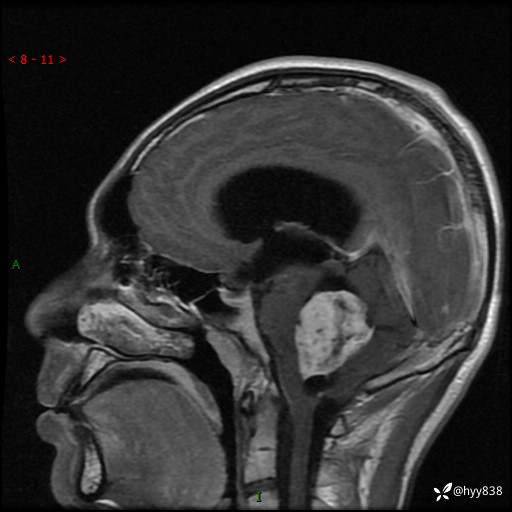

病例花季少年,头痛伴间断性呕吐1月余。四脑室占位,容易诊断错---结果公布~

性别:男

年龄:17岁

简要病史:头痛伴间断性呕吐1月余,外院CT提示颅脑占位

颅脑MRI平扫+增强